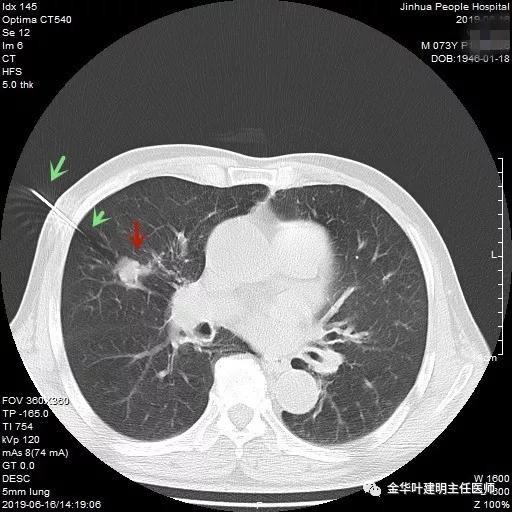

吴某不同意肺穿刺,咳嗽咳痰好转后就出院了。此后于今年6月份回院复查,仍然住在内科,这次想通了,同意肺穿刺,结果病理果然是肺癌,是低分化鳞癌。因为吴某与本院一院级领导是同村的,便让我去会诊。我觉得虽然从病灶来看可以手术,纵隔内也无明显转移的肿大淋巴结,相关检查也无远处转移证据。但患者年纪较大,平时有慢支与肺气肿,发作时还有喘憋症状,肺功能也示重度混合型通气功能障碍,MVV重度下降。询问吴某,平时一口气走上3楼是有困难的,所以行右肺上叶切除术后出现呼吸功能不全的概率还是比较高的,手术存在较大风险。争取手术也是为争取根治以至得到较长期生存的机会。若同意手术,也要家属与患者都十分理解,并对术后需要呼吸机辅助以及无法脱离呼吸机支持都有充分的思想准备。而若放弃手术,则主要是免疫治疗及放化疗,其中放化疗对肺功能也有一定影响,且无法达到根治的目的。我当时告诉吴某儿子,要开,做好术后出现呼吸功能衰竭的准备,且不能责怪我的同事和我本人;若暂不手术,也可回当地考虑保守治疗;当然也可先戒烟、锻炼肺功能、使用支气管扩张剂等改善肺功能,较短时间内再回院复查肺功能,再争取手术。吴某当时办理了出院手续,也没有与我们确认是否考虑手术。下面是当时6月份时候的片子以及肺穿刺情况:

绿色箭头示穿刺针,红色箭头示肿瘤